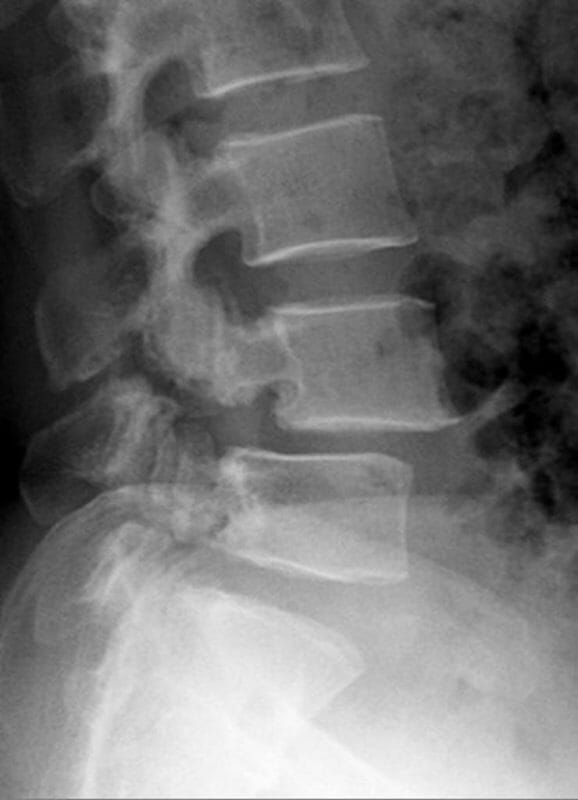

การวินิจฉัยโรคหมอนรองกระดูกสันหลังเคลื่อนประกอบด้วยการตรวจร่างกาย การถ่ายภาพรังสีเอกซเรย์ CT scan และการทำ MRI ในกรณีที่สงสัยภาวะกระดูกสันหลังเคลื่อนจนกดทับเส้นประสาท

ภาพถ่ายรังสีเอกซเรย์ในผู้ป่วยหมอนรองกระดูกสันหลังเคลื่อน

- อาจเห็นรอยหักของกระดูกสันหลังในชิ้นส่วนกระดูกที่เรียกว่า Pars Interarticularis

- มีการเคลื่อนตัวออกจากกันของแนวกระดูกสันหลัง

- พบความไม่มั่นคงของกระดูกสันหลังในภาพถ่ายในท่า ก้มและแอ่นหลัง (Flexion-Extension Lateral view)